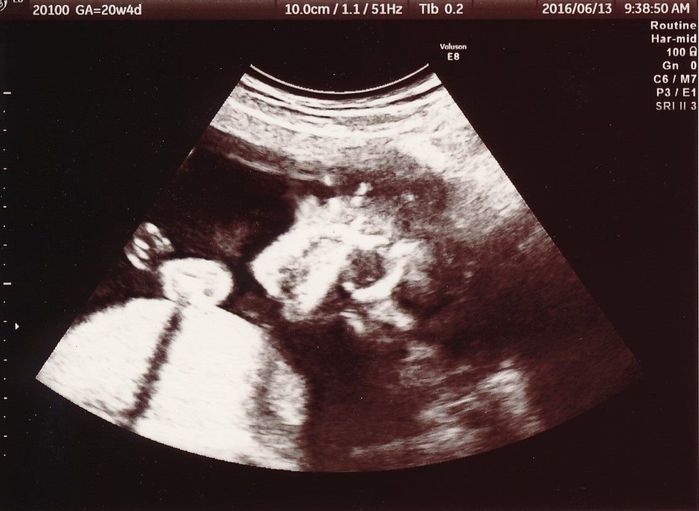

妊娠20週目のエコー写真

少し分かりにくいのですが、中央右寄りにある黒丸2つが赤ちゃんの目です。その左側にある両手で顔を隠しているようにも見えます。このような写真が手元に残っているということは、その回の健診では赤ちゃんがなかなかお顔を見せてくれなかったということになります。